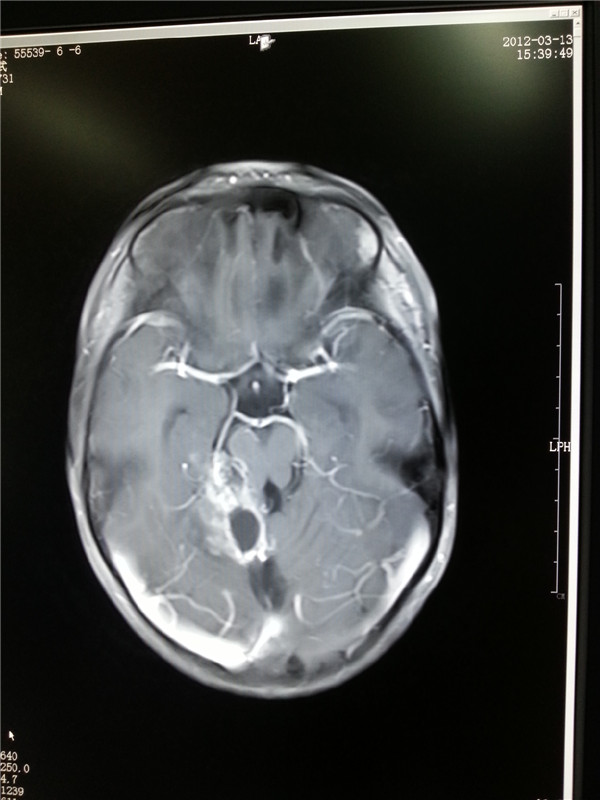

2011治疗前白点为3×2×2肿瘤(左图);2012复查肿瘤明显缩小(右图)